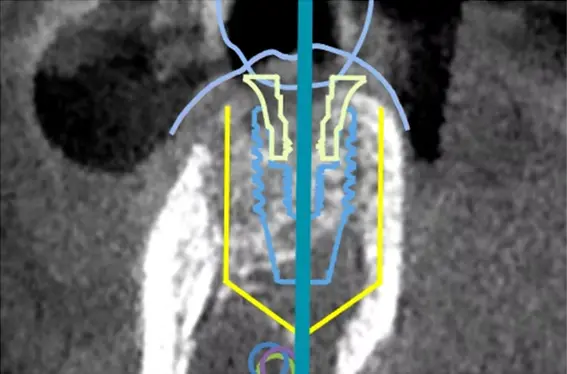

当院では、すべてのインプラント治療に「ナビゲーションシステム(Xガイド)」を導入しています。

Xガイドは、歯や骨の状態に加え、神経や血管の位置を含めた3D画像を手術中にリアルタイムで表示し、インプラントの埋入位置と角度を正確にナビゲートするシステムです。

このシステムでは、赤外線カメラを用いた光学式トラッキング技術により、ドリルの位置、角度、深さをリアルタイムで画面に表示します。これにより、術前に立てたCTベースの治療計画と、実際の手術操作を常に照合しながら治療を進めることができます。

ナビゲーションシステム(Xガイド)の画像

Xガイドは現在、世界30か国以上で導入されており、その信頼性と技術力が評価されているシステムです。当院では、こうした技術の力も活かしながら、精度と安心に配慮したインプラント治療を日々提供しています。